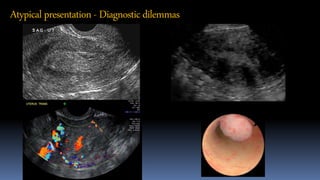

Atypicalpresentation- Diagnosticdilemmas

Atypical presentation - Diagnosticdilemmas

Atypical presentation -Diagnosticdilemmas